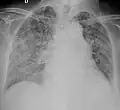

Tuberculosis of the lungs

Testing for miliary tuberculosis is conducted in a similar manner as for other forms of tuberculosis, although a number of tests must be conducted on a patient to confirm diagnosis.[3] Tests include chest x-ray, sputum culture, bronchoscopy, open lung biopsy, head CT/MRI, blood cultures, fundoscopy, and electrocardiography.[9] The tuberculosis (TB) blood test, also called an Interferon Gamma Release Assay or IGRA, is a way to diagnose latent TB. A variety of neurological complications have been noted in miliary tuberculosis patients—tuberculous meningitis and cerebral tuberculomas being the most frequent. However, a majority of patients improve following antituberculous treatment. Rarely lymphangitic spread of lung cancer could mimic miliary pattern of tuberculosis on regular chest X-ray. [14]

A case of miliary tuberculosis in an 82-year-old woman: